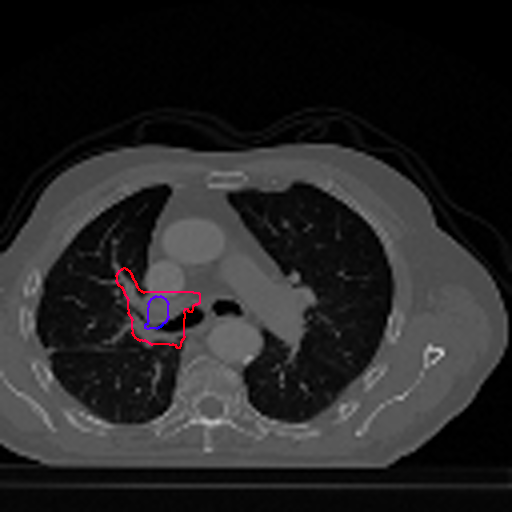

Figure 5 shows a comparison between predictions by the MultiResUNet model and Deeply supervised MultiResUNet model. It can be seen that the latter can delineate the tumor edges more accurately than the former. The ground truth (shown in red) and the prediction (shown in blue) have a more consistent alignment with each other in Deeply Supervised MultiResUNet’s prediction.

However, in a few rogue cases, where the shapes of the ground truth are exceedingly uncoordinated, perhaps with fissures in the middle or with erratic outlines, it is seen that the predicted tumor regions are prone to imperfections. Although for these cases, our model can predict the existence of tumors, the shapes can often appear to have disfigurements. This is demonstrated in Figure 6. We plan on addressing this issue in our future work.